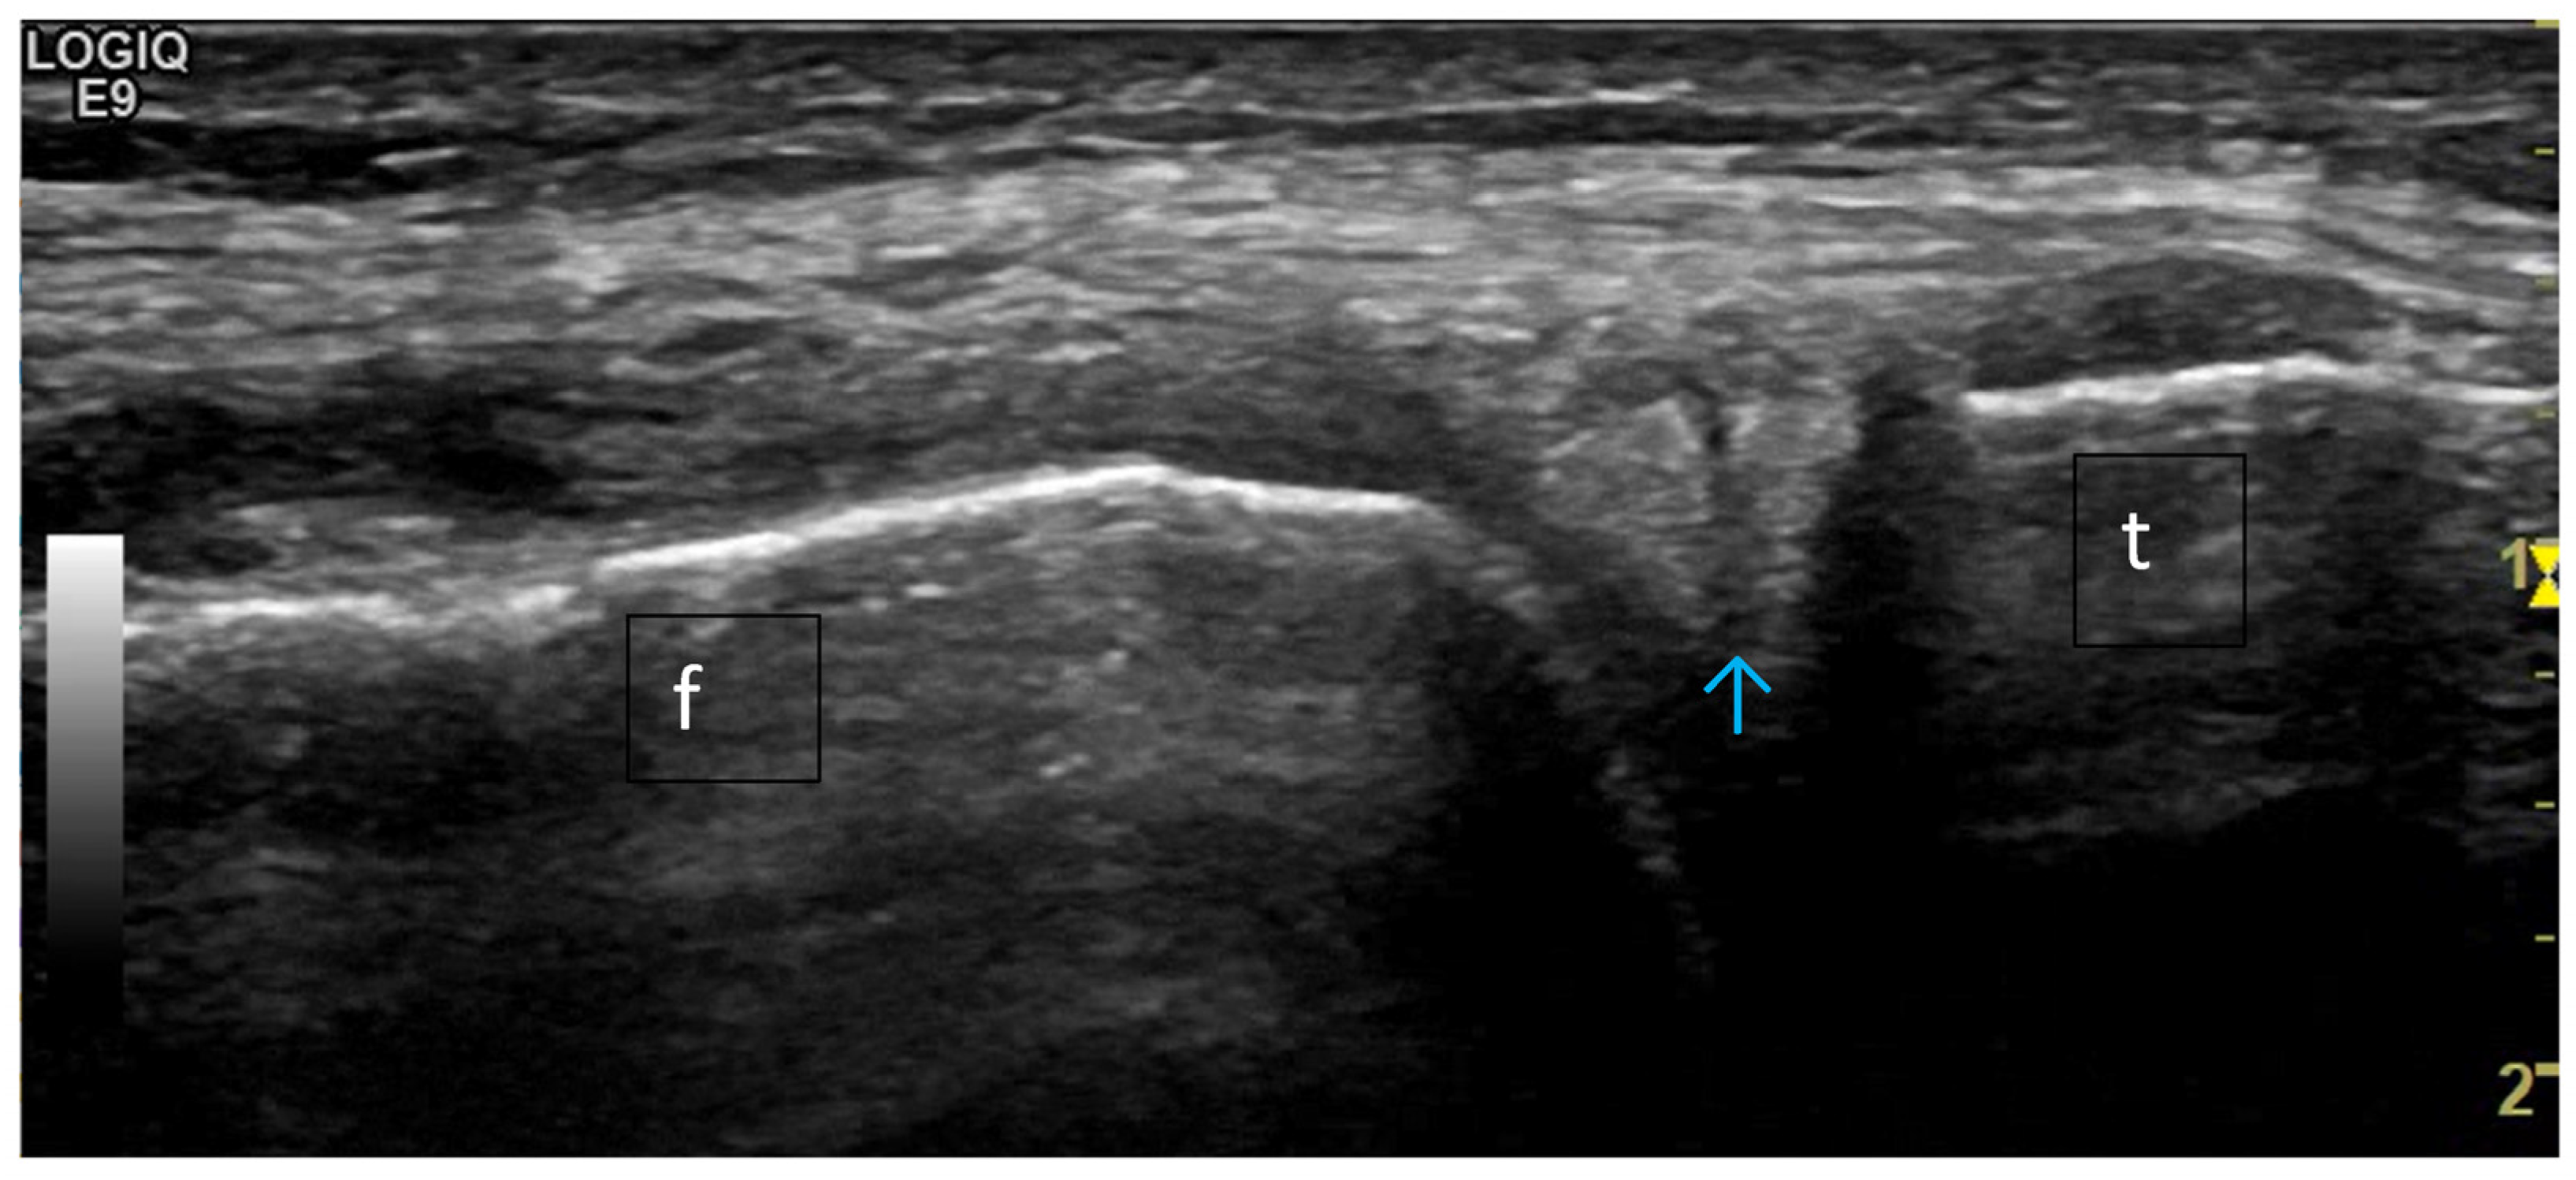

4. Examples of US Phenotypes